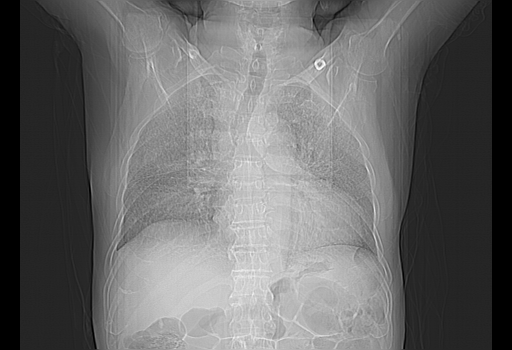

今天复查肺部CT,发现双肺广泛磨玻璃样改变。所以我把3月19日和5月9日相隔50天的肺部CT上传。请大家会诊。

5月9日肺部CT(在4月27日齐鲁医院肺部CT描述部分肺组织磨玻璃样改变,12天后肺组织广泛磨玻璃样改变)

大致读了系列胸部CT:纵隔窗无明显异常,肺窗:从4、27至今:主要是双肺中下野外带可见毛玻璃样改变,目前处于急性肺泡炎阶段,至于原因考虑1、结替组织或胶原血管性疾病所致?2、恶性疾病如恶组在肺部所致的表现或细支气管肺泡癌?3、药物或其它原因如肺蛋白沉着症所致肺泡炎目前不太可能?总之,明天就去请我院的呼吸科、感染科、血液科和临免专家会诊哈。